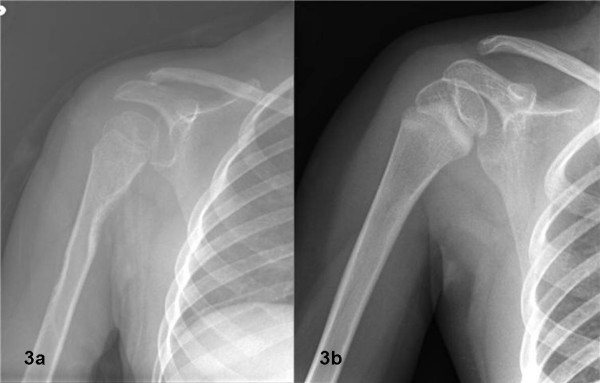

Рентген плечевого сустава в двух проекциях (прямой и боковой снимок) показывает довольно подробную картину патологических изменений. Кроме состояния самого сочленения, с его помощью можно оценить состояние ключицы и лопатки. Благодаря прямой проекции врач определяет степень смещения переломов (если таковые есть), на боковых снимках (аксиальных) хорошо видны изменения краев вертлужной впадины.

Признаки травм плеча на снимках

Так, при переломах, обычно происходящих с ключицей или плечевой костью, видна линия нарушения целостности костных формирований (также она визуализируется при наличии трещин). Она может быть единственной, когда перелом не осложненный. Но при наличии осколков таких линий бывает несколько. Также на снимках определяется и степень повреждения осколками мягких тканей. При вывихах, когда головка плечевой кости «выворачивается» из суставной впадины, это также четко фиксируется на рентгенограммах.

Изучив несколько проекций плеча, можно определить, в какой точке произошел разрыв капсулы сустава, поврежден ли суставной хрящ. Также легко можно «увидеть» наличие обширных гематом (кровоизлияний), разрывы связок и мышц.